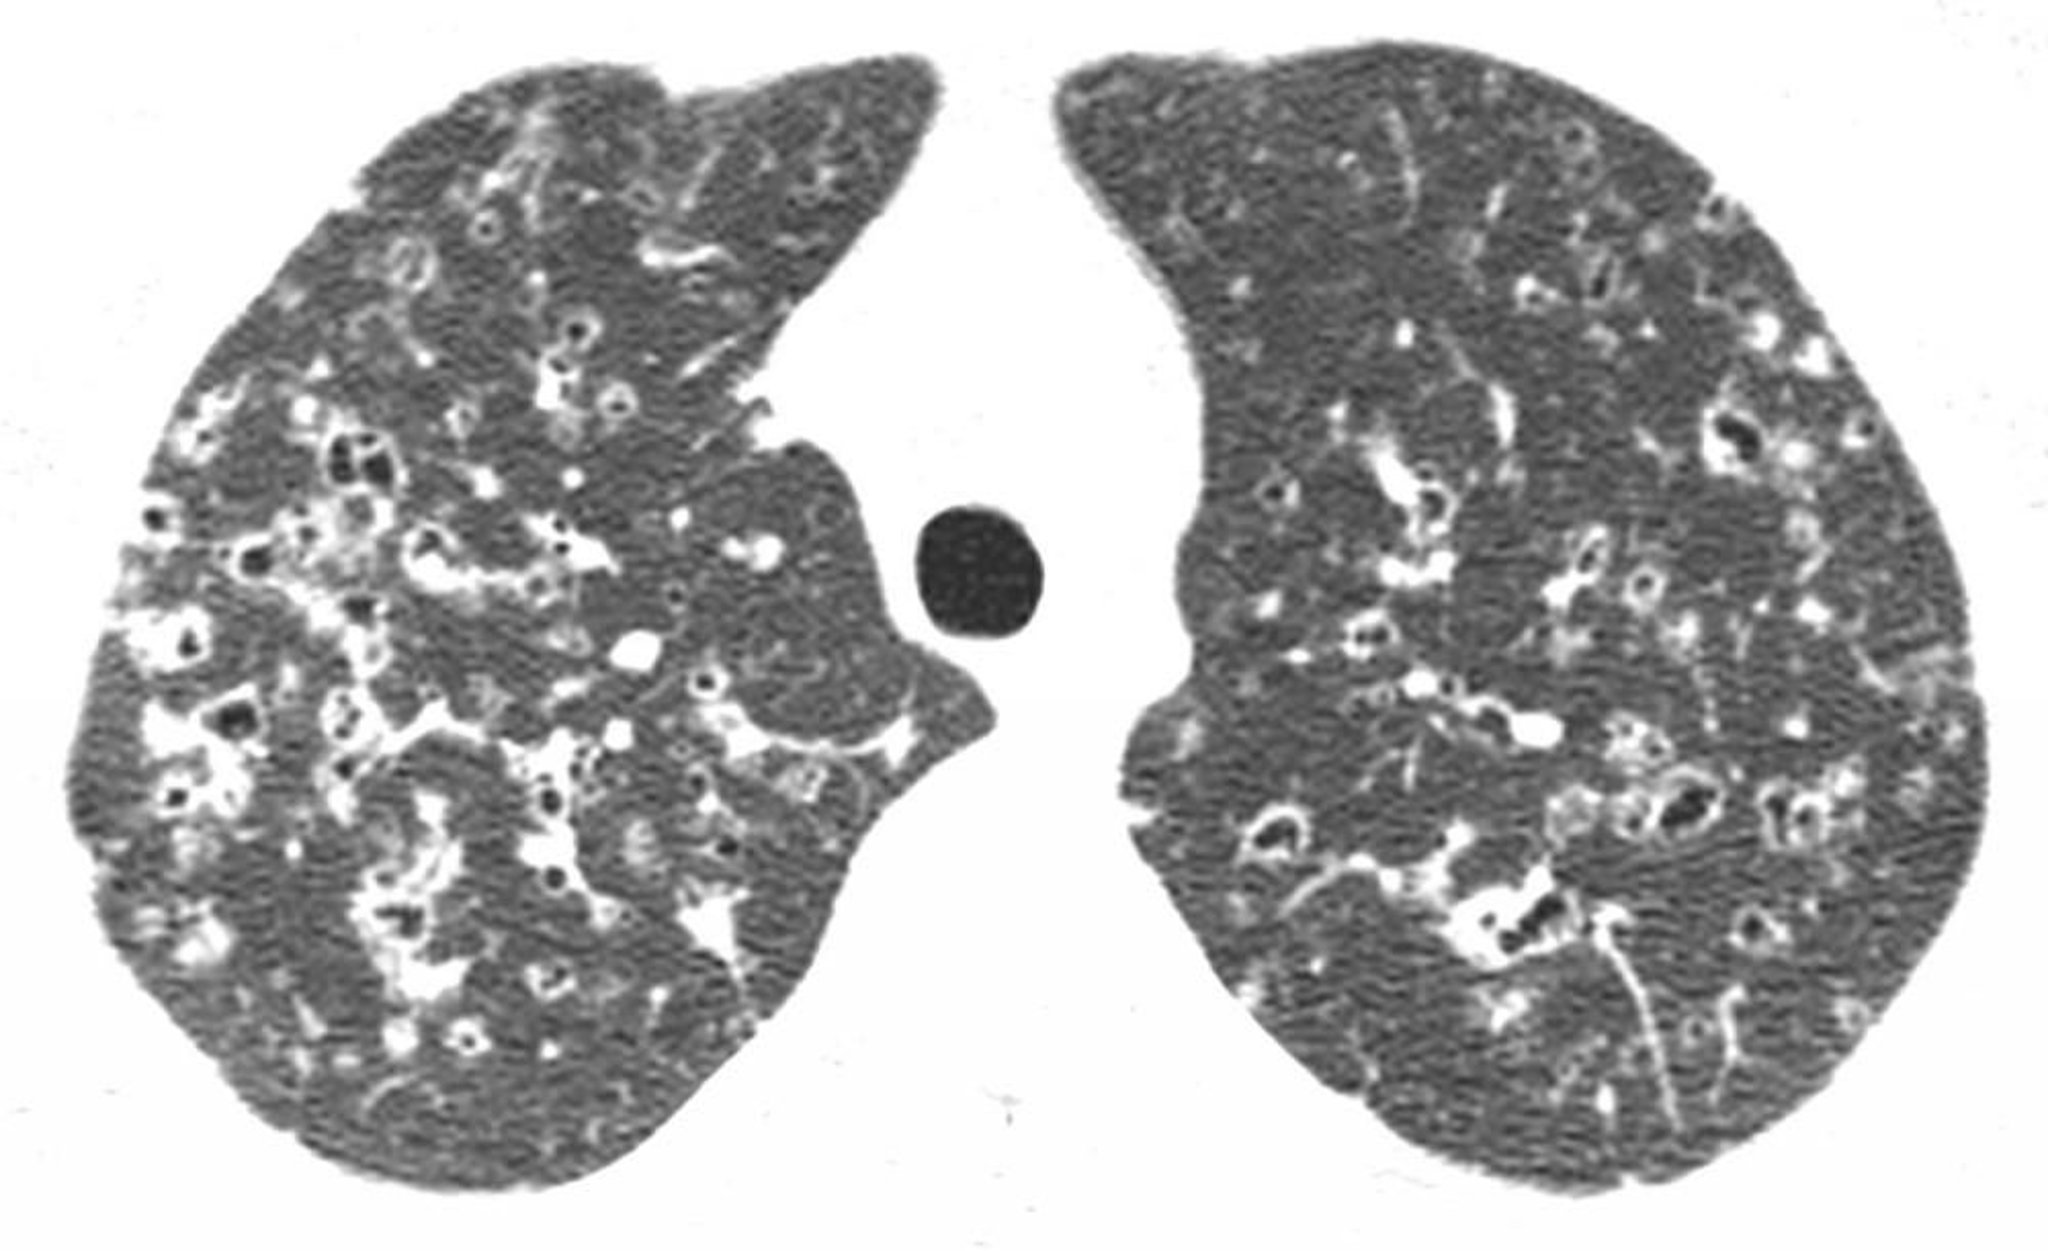

上葉の高分解能CT上で,通常は上葉および中葉領域に,結節および含気を伴う不規則な嚢胞がみられる。このような所見は喫煙歴のある患者におけるランゲルハンス細胞組織球症に特徴的である。

Image courtesy of Harold R.Collard, MD.